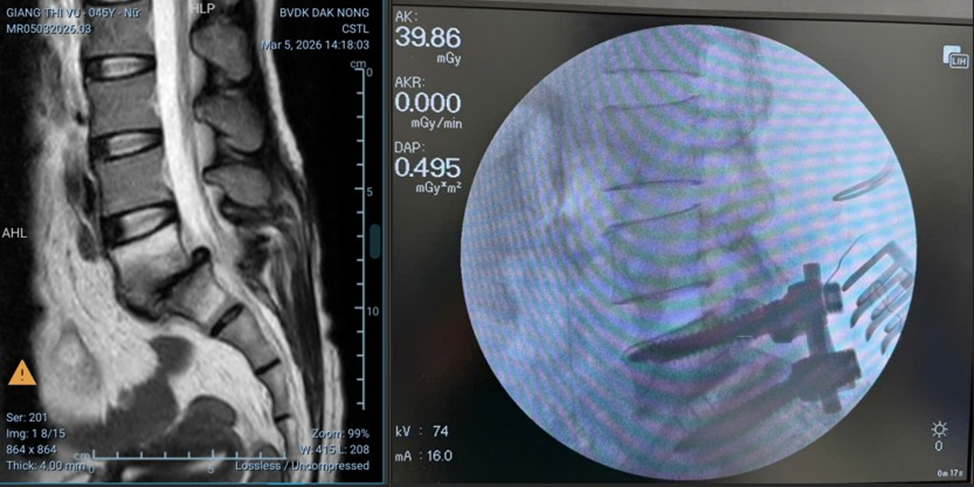

Qua chụp cộng hưởng từ (MRI), các bác sĩ xác định các bệnh lý cột sống phức tạp như: hẹp ống sống, trượt đốt sống và thoát vị đĩa đệm, từ đó chỉ định phẫu thuật. Đội ngũ y, bác sĩ đã tiến hành giải ép tủy, rễ thần kinh, kết hợp bắt vít cố định cột sống và thay đĩa đệm nhân tạo.

Với sự hỗ trợ của trang thiết bị hiện đại như máy chụp cộng hưởng từ (MRI) và sự tận tâm của các bác sĩ, điều dưỡng, cả hai ca phẫu thuật đã được thực hiện thành công, an toàn.